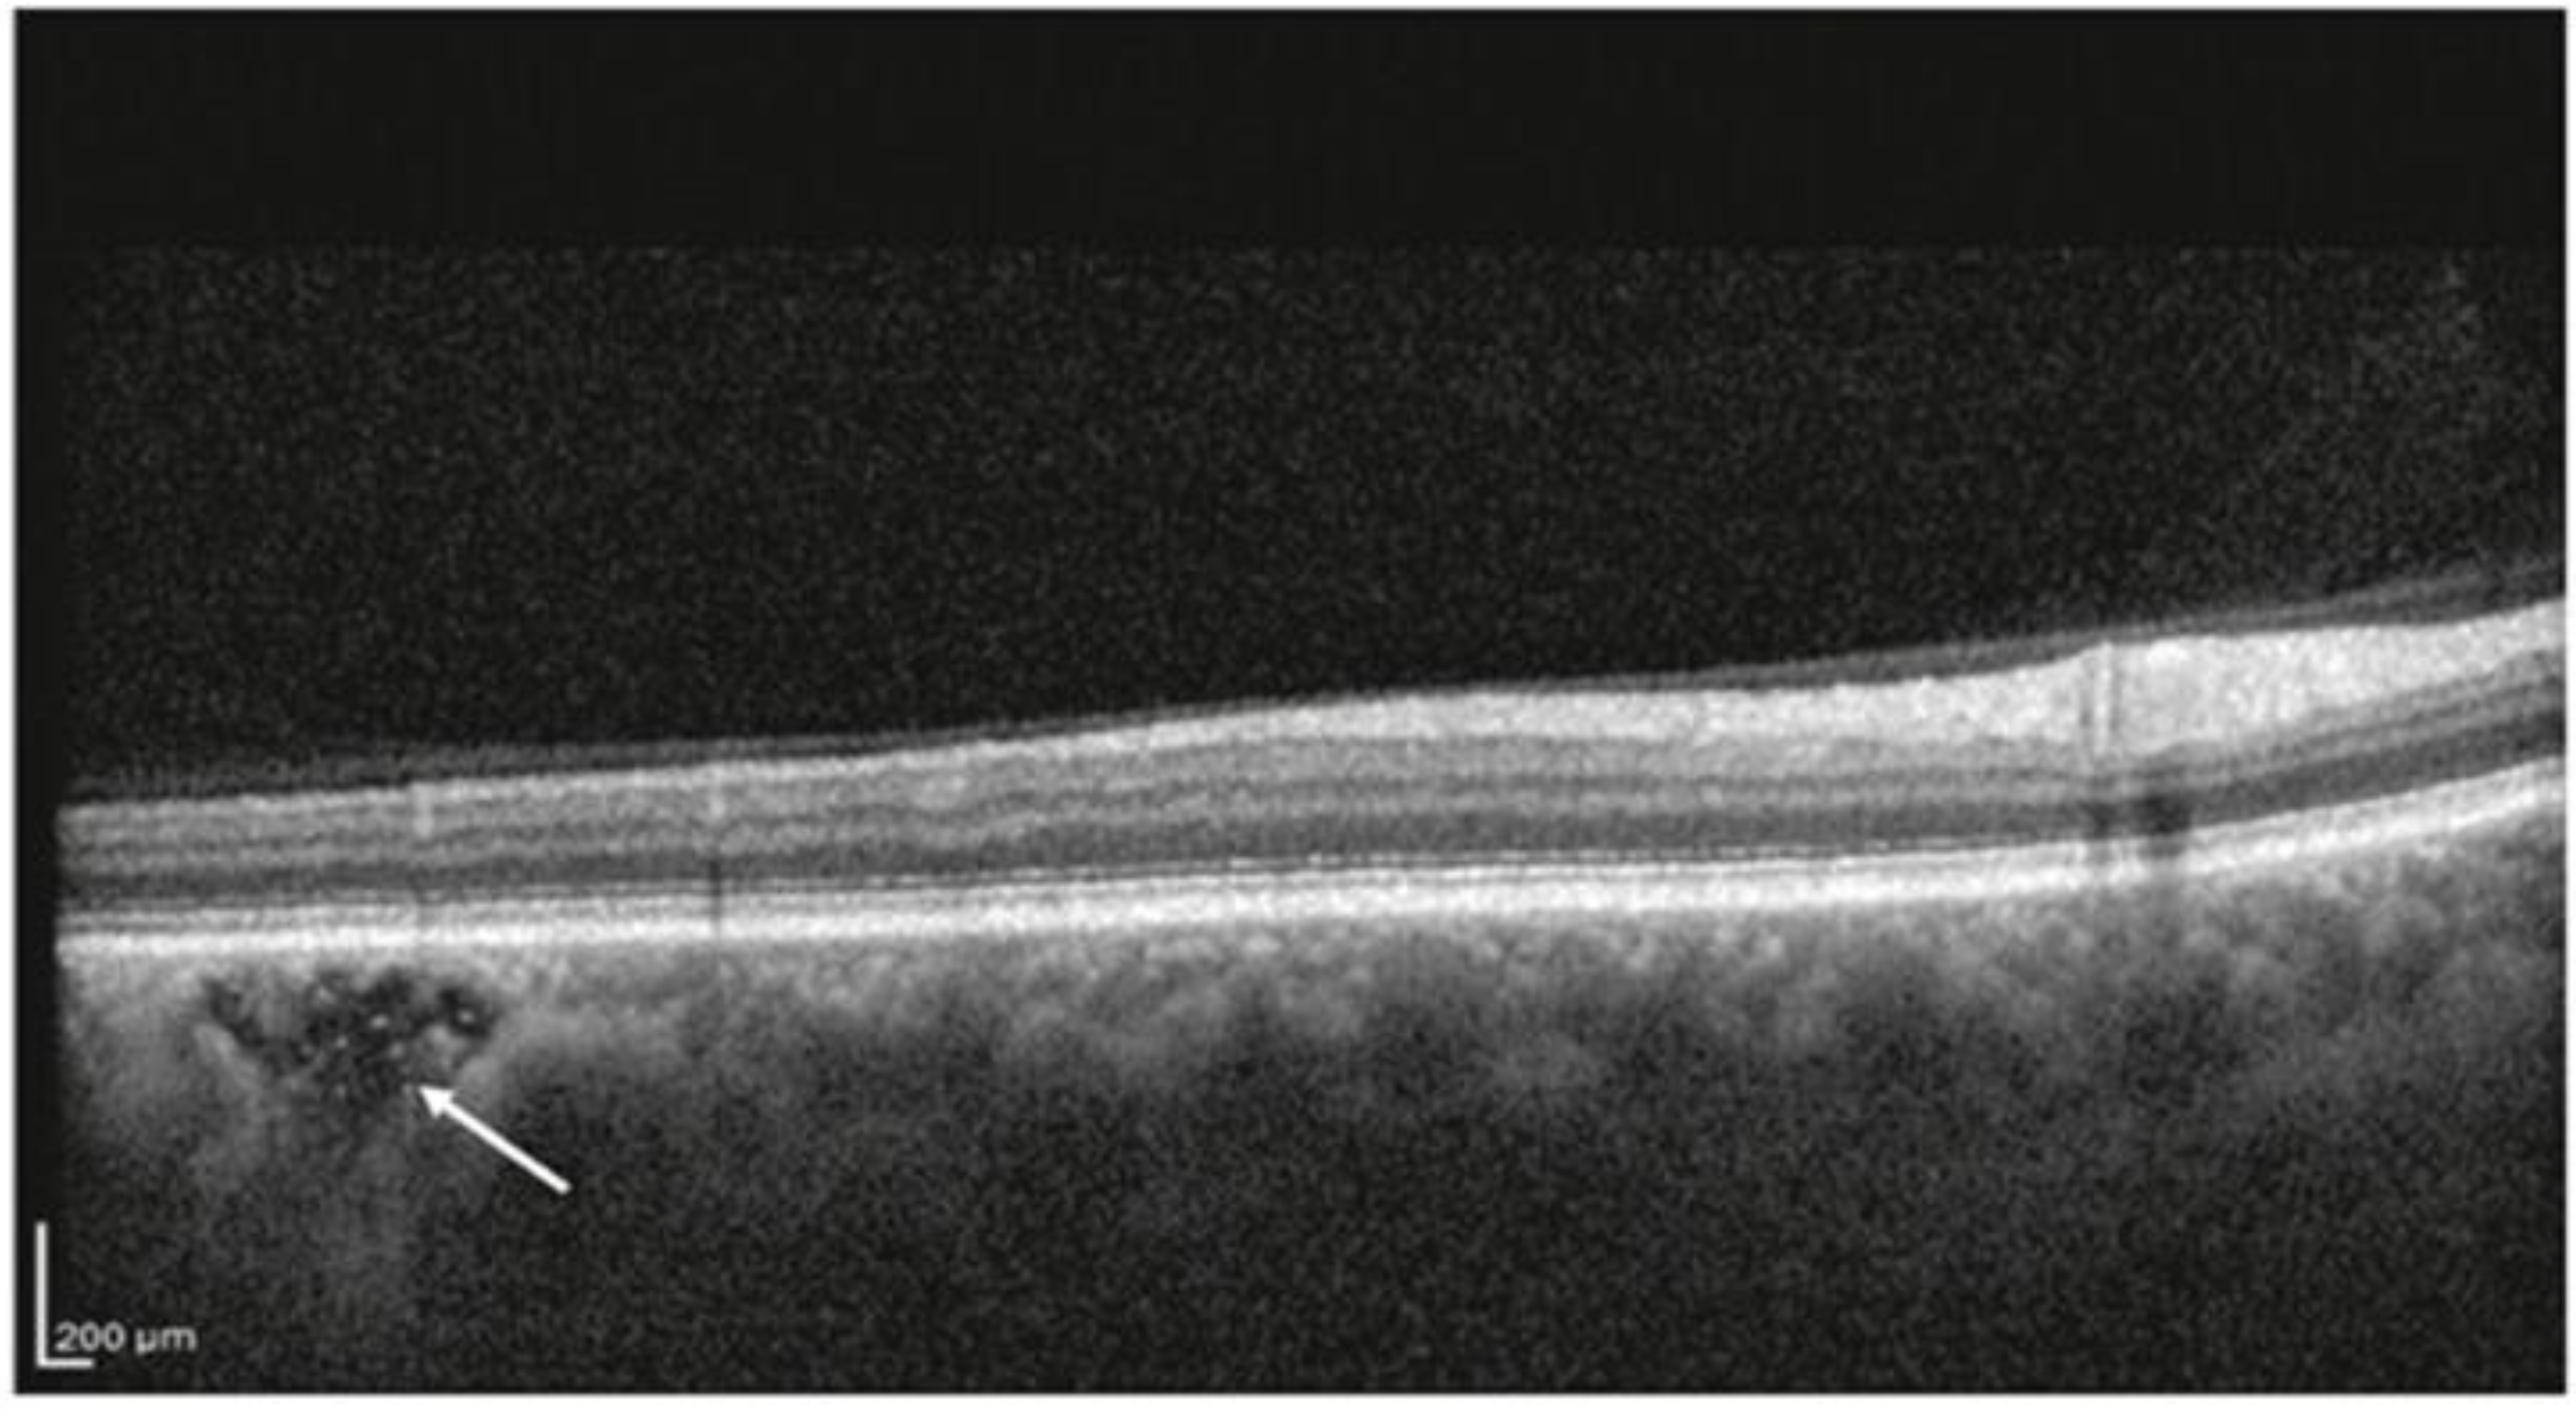

2.6. Choroidal Caverns or Choroidal Lipid Globules

- Dolz-Marco, R.; Glover, J.P.; Gal-Or, O.; Litts, K.M.; Messinger, J.D.; Zhang, Y.; Cozzi, M.; Pellegrini, M.; Freund, K.B.; Staurenghi, G.; et al. Choroidal and Sub-Retinal Pigment Epithelium Caverns: Multimodal Imaging and Correspondence with Friedman Lipid Globules. Ophthalmology 2018, 125, 1287–1301. [Google Scholar] [CrossRef] [PubMed]

- Friedman, E.; Smith, T.R. Clinical and pathological study of choroidal lipid globules. Arch. Ophthalmol. 1966, 75, 334–336. [Google Scholar] [CrossRef]

- Querques, G.; Costanzo, E.; Miere, A.; Capuano, V.; Souied, E.H. Choroidal Caverns: A Novel Optical Coherence Tomography Finding in Geographic Atrophy. Investig. Ophthalmol. Vis. Sci. 2016, 57, 2578–2582. [Google Scholar] [CrossRef]

- Sacconi, R.; Borrelli, E.; Marchese, A.; Gelormini, F.; Pennisi, F.; Cerutti, A.; Bandello, F.; Querques, G. Re: Dolz-Marco et al. Choroidal and sub-retinal pigment epithelium caverns: Multimodal imaging and correspondence with Friedman lipid globules (Ophthalmology. 2018;125:1287–1301). Ophthalmology 2019, 126, e53–e54. [Google Scholar] [CrossRef]

- Guo, X.; Zhou, Y.; Gu, C.; Wu, Y.; Liu, H.; Chang, Q.; Lei, B.; Wang, M. Characteristics and Classification of Choroidal Caverns in Patients with Various Retinal and Chorioretinal Diseases. J. Clin. Med. 2022, 11, 6994. [Google Scholar] [CrossRef]